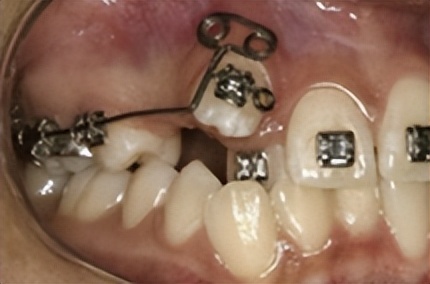

需拔牙矫治的牙齿拥挤病例

矫正经典拔牙模式: 拔除上下左右4颗双尖牙

一般来说,正畸拔牙以后的间隙可以被两个方面的牙齿移动所关闭,一方面前牙向后移动,另一方面是后牙向前移动。

根据模型测量和X线影像分析结果,如果牙列拥挤严重或前突,则需要拔牙间隙更多的用于前牙往后移动;如果后牙咬合关系不佳,则通过后牙更多地向前移动来调整。

正畸医生通过矫治器的作用有效控制牙齿移动,最终将拔牙间隙完全关闭,因此是不需要镶牙的。